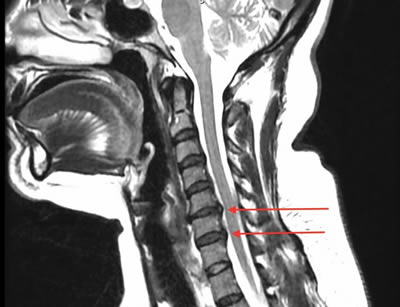

IMÁGENES

Galería de imágenes